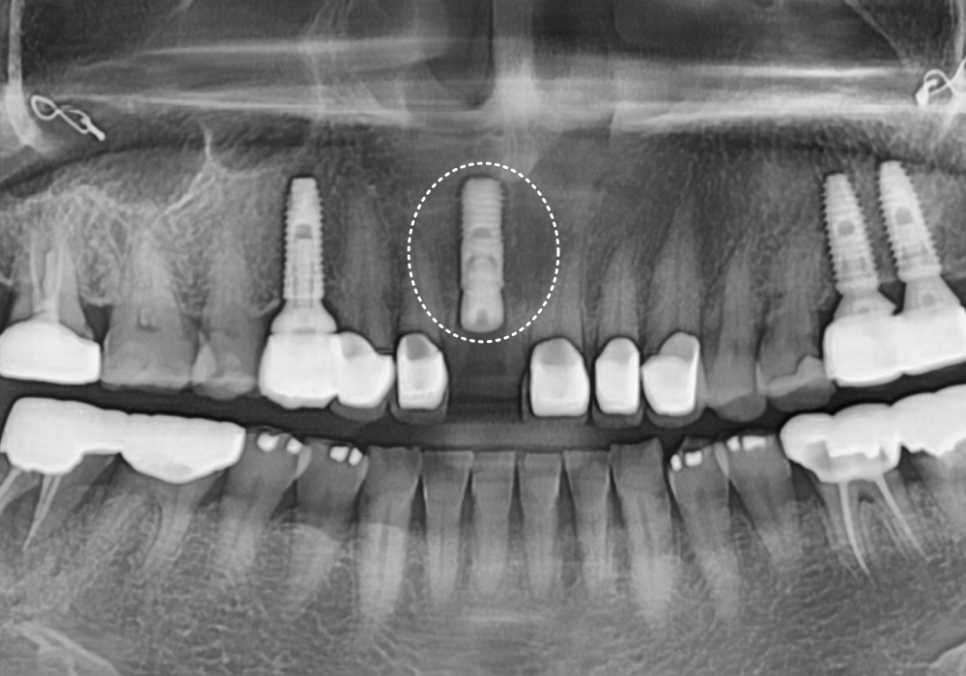

여기서 가장 공을 들여야 할 부분은 무엇일까요?

바로 기존에 먼저 해두었던

다른 앞니 보철물들과

색상을 감쪽같이 맞추는 일입니다.

위의 사진처럼 새로 만든 치아가

유독 하얗게 둥둥 떠 보인다면

아무리 튼튼하게 잘 심었어도

성공적인 치료라고 말하기는 어렵겠죠.

주변 치아들과 마치 원래부터 하나였던 것처럼

자연스럽게 어우러지도록 만드는 데

가장 많은 정성을 쏟았습니다.

드디어 완성된 모습입니다.

어떤 게 임플란트인지 한눈에 찾기 어려우시죠?

241101

색상은 물론이고 모양까지

주변 치아와 참 잘 어우러져서

환자분도 저도 무척 만족스러웠던 사례였습니다.^^